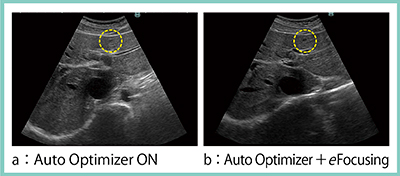

ARIETTA 850には,ゲイン最適化機能“Auto Optimizer”が搭載されている。これは,自己学習機能で,50回フリーズしたときのゲイン値を学習し,以降は学習した平均のゲイン値で画像が表示されるようになる。これにより,ゲイン設定が微調整ですむようになり,ワークフローの短縮につながる。特に,eFocusingにこのAuto Optimizerを追加することで適正ゲインが保たれるため,存在診断の向上につながると考えられる。

そこで,肝囊胞症例で検証した画像を提示する。浅部の肝囊胞症例(図4)である。Auto Optimizerだけ(図4 a)ではフォーカスが合っていないため病変が不明瞭であるが,eFocusingを追加(b)することで,フォーカスを設定しなくても病変がはっきりと描出された。

図4 Auto Optimizerとの併用におけるeFocusingの有用性

(浅部の肝囊胞,S3,7mm)